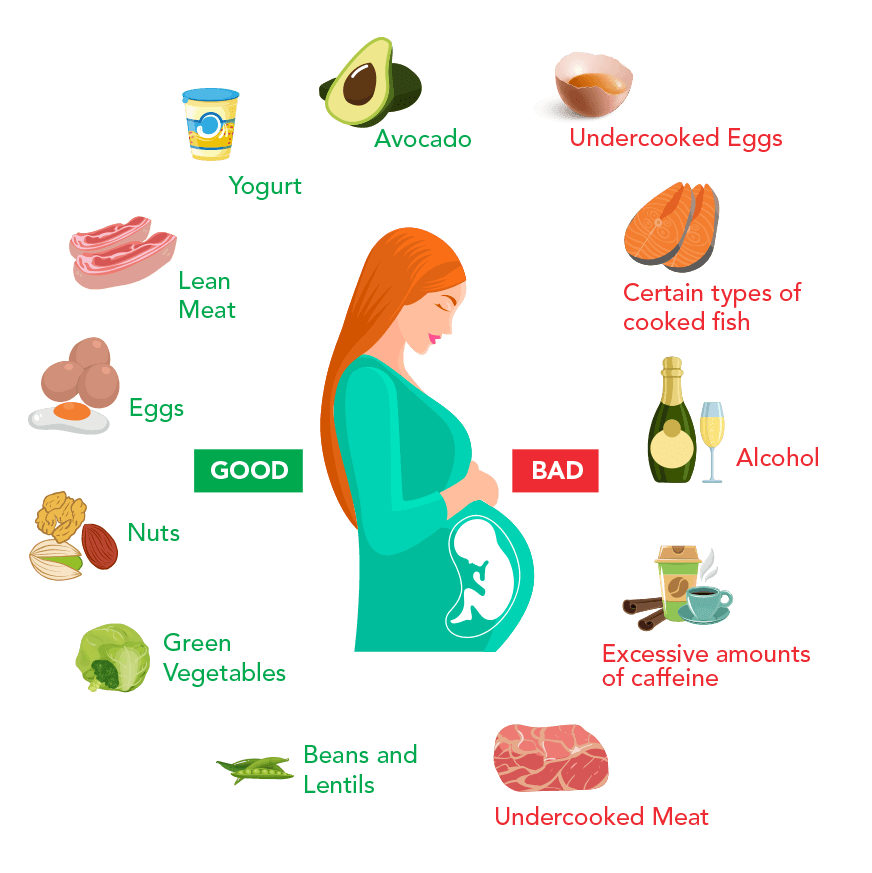

Lifestyle factors:

Unhealthy lifestyle determinants the reasons for low-lying placenta during pregnancy. It has been observed that excessive cigarette smoking and drug use such as cocaine are causes for a low placenta. This is because excessive smoking may lead to excessive carbon monoxide hypoxemia in the blood which results in placental hypertrophy. Placental hypertrophy is clinically defined as an abnormally heavy or disproportionate placenta. If a placenta is too heavy,

it would be particularly difficult for it to move upwards due to gravitational forces.

Alcohol consumption also has a direct effect on the placenta in Indian women. Though it doesn’t technically cause placenta previa, it does cause placental abruption which is an equally serious complication during pregnancy. A placental abruption is when the placenta detaches itself from the inner walls of the uterus, thus depriving the baby of oxygen and important nutrients.